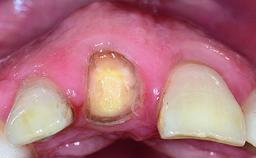

A 32-year-old female Caucasian patient with a compromised maxillary right central incisor was referred to us by a general dentist. Her chief complaints were discomfort and mobility of tooth 11 with unsatisfactory esthetics due to discoloration. The patient reported a previous trauma, some years earlier, as the origin of pathology on the afflicted tooth. Anamnesis was negative for any other dental or periodontal pathology in the remaining dentition. The patient did not take any medication and reported to be a light smoker (5–10 cigs/day). She had high esthetic expectations of her treatment. The extraoral examination revealed a high smile line with full exposure of her maxillary teeth and surrounding soft tissue in the area between the second premolars.

Soft Tissue Anatomy Intact Defective

Bone Volume Horizontally and vertically sufficient Horizontally deficient Deficient vertically or deficient vertically AND horizontally

Bone Volume Deficient horizontally, requiring prior grafting